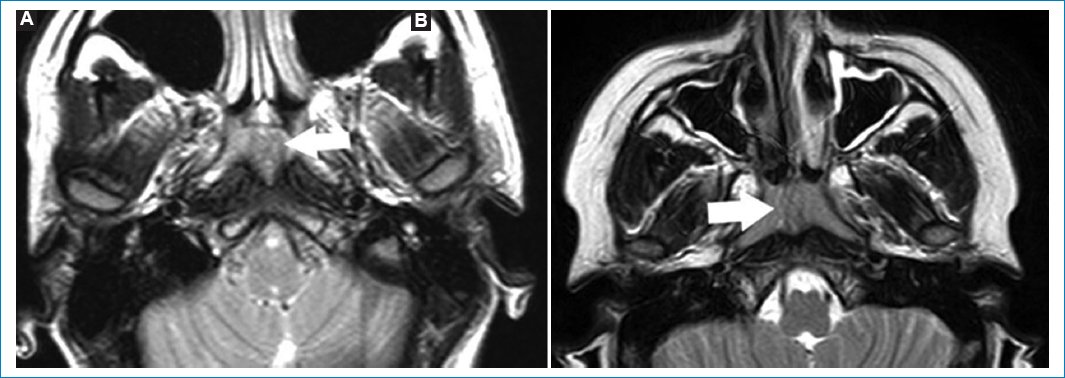

La efusión del ápex es acúmulo del líquido estéril, sin asociarse a síntomas clínicos. Las cavidades mastoideas presentan continuidad con el ápex petroso, por lo que pueden drenar su contenido en un ápex neumatizado29. Se objetiva hipointenso en T1 e hiperintenso en FLAIR y T2, sin realzar con gadolinio (Fig. 9)29.

Figura 9. Imágenes potenciadas en T2. Cortes: axial (A) y coronal (B). Se observa (flechas) colección en el ápex izquierdo. Esta es hiperintensa en T2, resaltando en comparación del ápex neumatizado contralateral.

La presencia de hiperintensidades en las celdillas mastoideas, valoradas en secuencias ponderadas en T2, suele denominarse mastoiditis (Fig. 10)30. Este es un hallazgo fortuito, cuando la RM se pide por otro motivo; incluso algunos estudios de cohorte sugieren no mencionar la palabra mastoiditis, reemplazándola en el informe por ocupación de cavidades mastoideas. Cuando se encuentre la presencia de hiperintensidades en las cavidades mastoideas, deberá correlacionarse con la clínica, antes de denominarse mastoiditis30.

Figura 10. Corte axial (A) y sagital (B), potenciados en T2. Ocupación de cavidades mastoideas izquierdas (flechas), valoradas como hiperintensidades puntiformes y asimétricas.

Habitualmente la hiperintensidad se debe a acumulación de líquido estéril, por disfunción tubárica30.